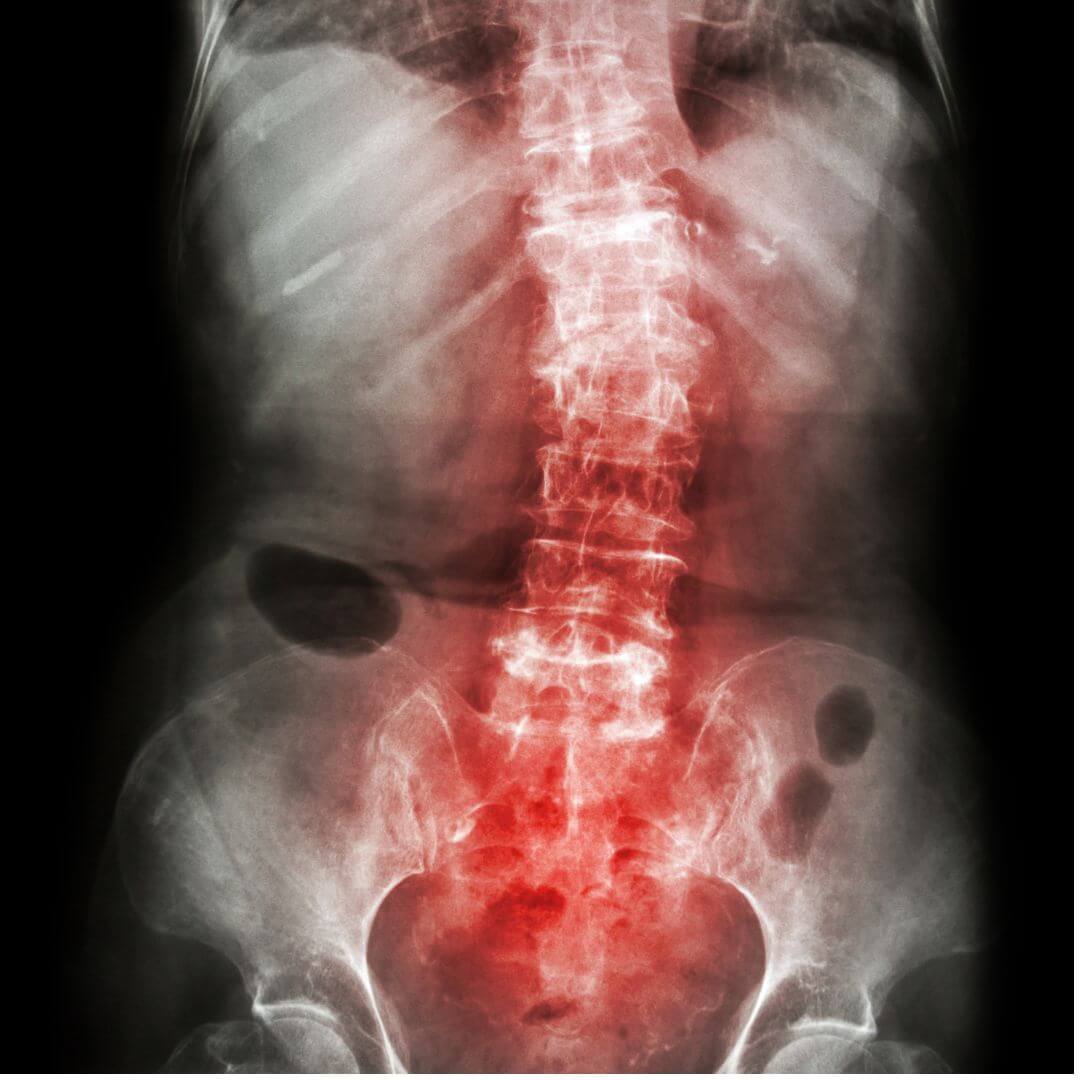

Osteoporosis is a condition where your bones become weak and fragile, making them more likely to break or fracture, even from minor falls or bumps. Most people don’t feel symptoms until a fracture happens, which is why it’s often called a ‘silent disease.’

Osteoporosis is diagnosed on a Bone mineral density scan (BMD). A BMD scan is a simple, painless test that checks how strong your bones are. It’s a bit like an X-ray, but it uses very low levels of radiation to measure how much calcium and other minerals are in your bones. The more minerals, the stronger your bones usually are.